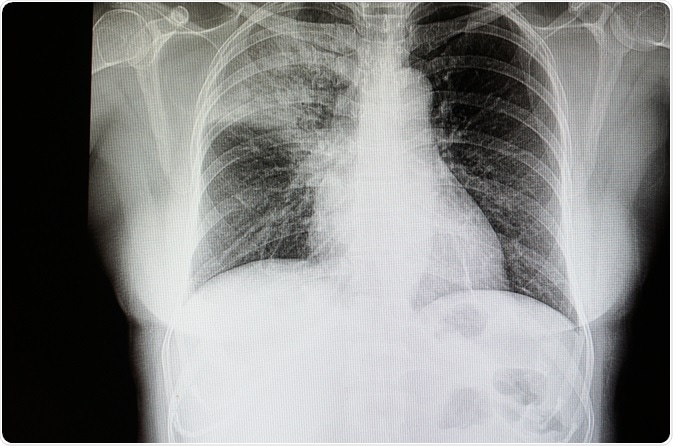

Image Credit: Tomatheart / Shutterstock.com